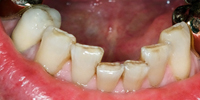

Die Abb. 1 bis 4 sollen als anschauliche Beispiele für gesunde und kranke Fundamente dienen.

Ein 31 Jahre alter Patient zeigt einen starke Zahnfleisch-Rückgang im Oberkiefer (Abb. 1 und 3) und wir beschliessen, diese Rezessionen zu behandeln.

Der Erfolg der Behandlung ist deutlich in den Abb. 2 und 4 zu sehen. Sehr augenfällig konnte die Situation um den Eckzahn im linken Oberkiefer verbessert werden (vergleiche dazu Abb. 3 vorher und Abb. 4 nachher).